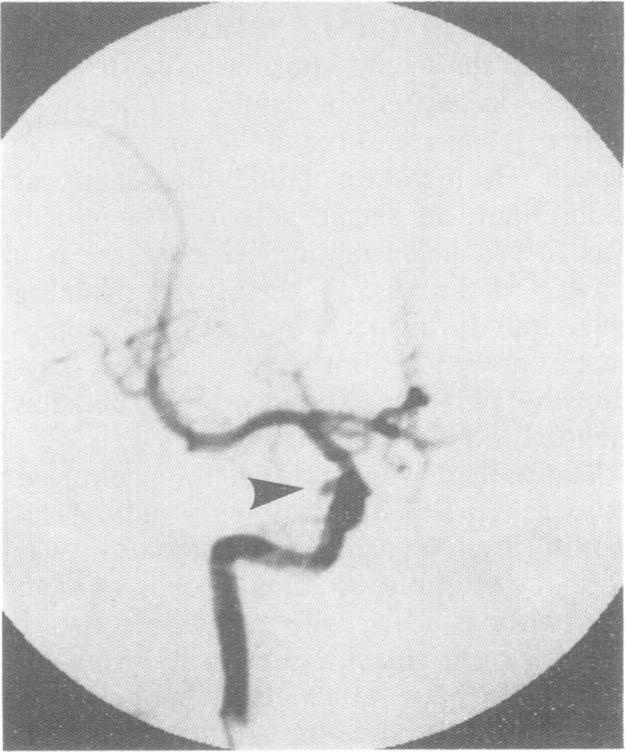

Isolated palsy of the fourth cranial nerve caused by an intracavernous aneurysm.

J Neurol Neurosurg Psychiatry. 1989 May;52(5):679. doi: 10.1136/jnnp.52.5.679.